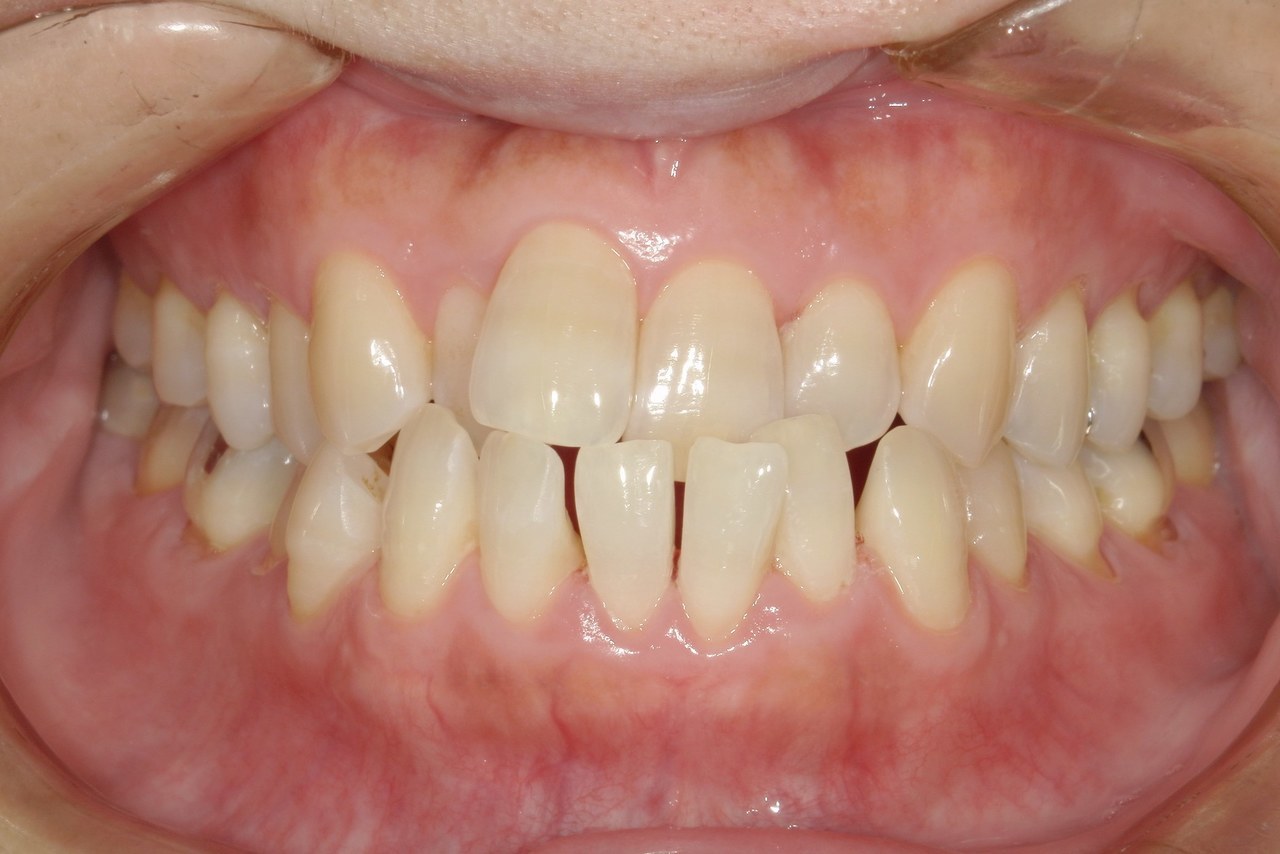

Before

浜松市中央区・自動車学校前駅のインビザラインの症例

M.I. 40代女性

上下の前歯をキレイに並べたい、中心がズレている、という主訴でご来院。上下前歯の叢生を治し、正中を合わせました。

治療の期間:R3. 4/13〜R5. 8/30

治療の価格:88万円